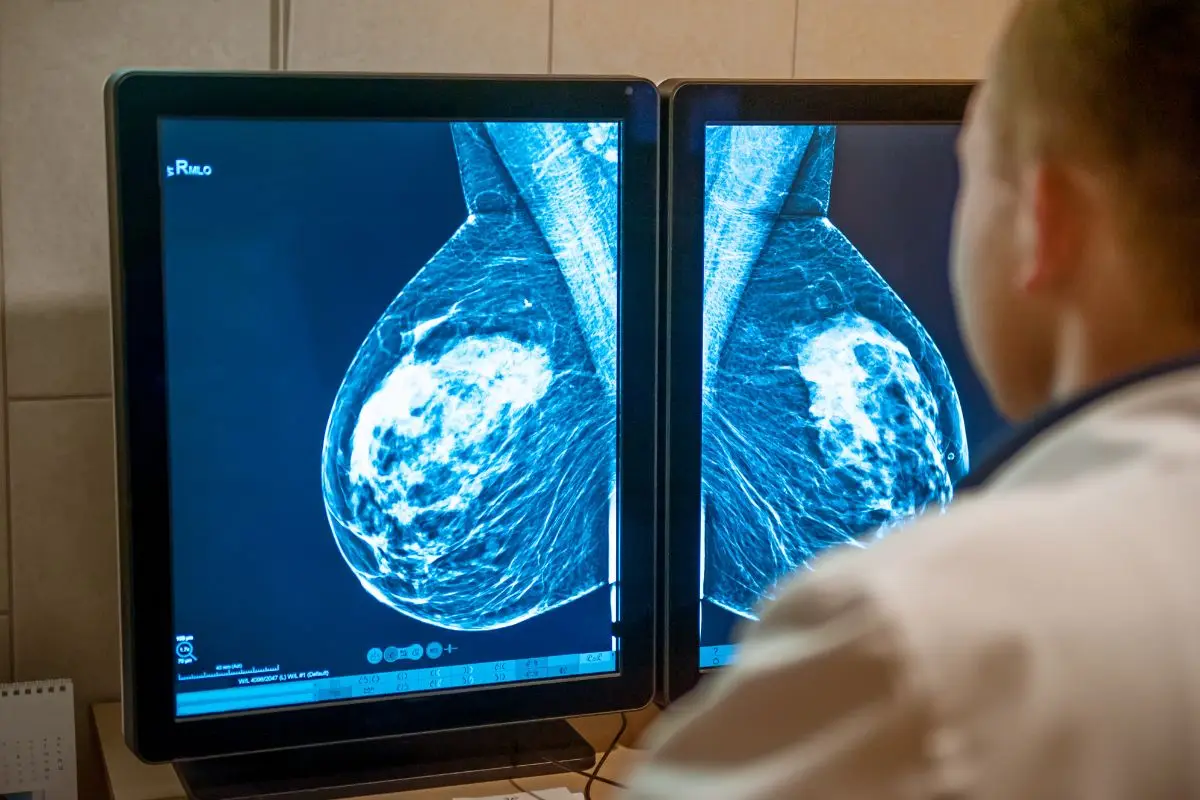

Una terrible situación, y que podría costar incluso con la vida de algunas mujeres, fue la que se detectó en la región del Biobío, con la confirmación que en la zona se realizaron 1.200 mamografías con resultados falsos.

Por ahora el llamado es urgente para aquellas mujeres que se realizaron su mamografía en Novakinem, considerando el diagnóstico que recibieron las 1.200 víctimas.

"Hay mujeres que podrían tener cáncer y no lo saben, mientras que otras quizás están sanas y viven la angustia de pensar que están enfermas", señala el reportaje.

La investigación se inició por las denuncias y querellas presentadas por ocho municipios del Bío Bío, los que contrataron con el laboratorio Novakimen la realización de mamografías para mil mujeres atendidas por la salud primaria.